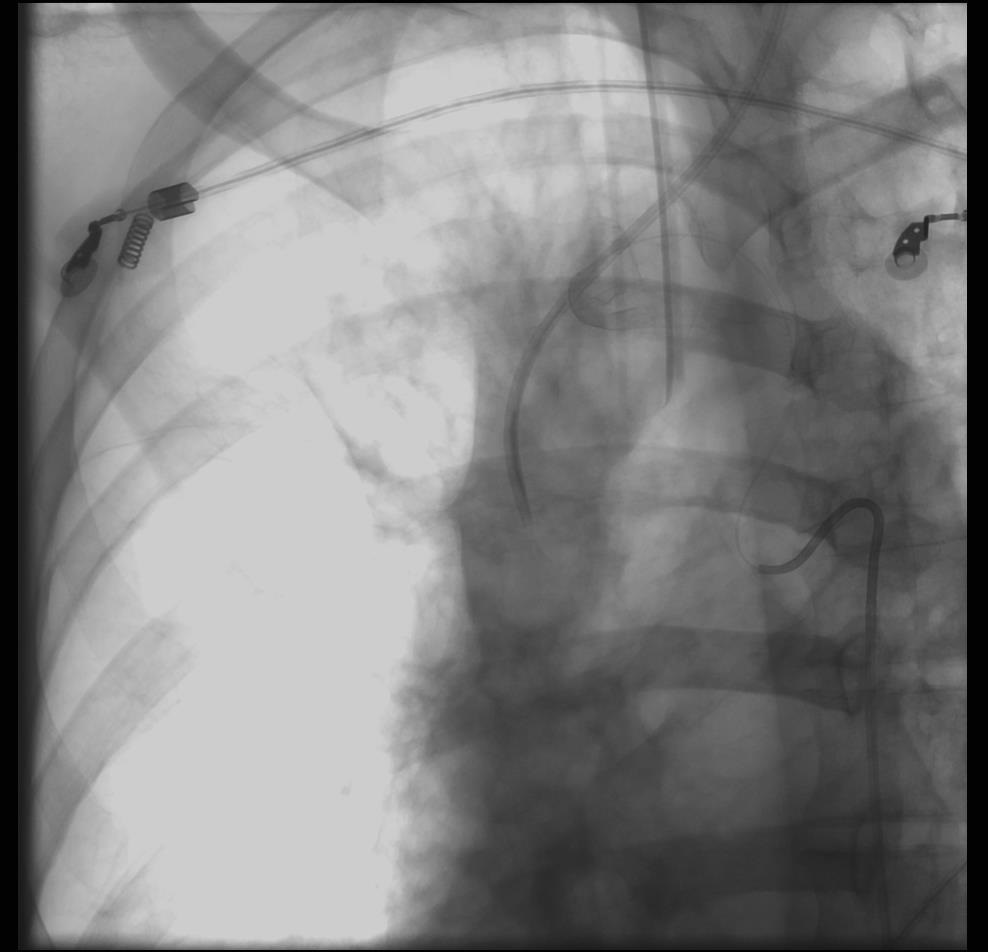

• 逆行静脉 Retrograde transvenous

• 经静脉血管塞 Transvenous Plug (+/- AVP)

• Push-through to arterial side